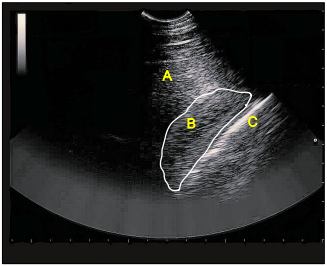

Na ultrassonografia, identifique as estruturas anatômicas abdominais observadas na imagem e assinale a alternativa correta.

Na ultrassonografia, identifique as estruturas anatômicas abdominais observadas na imagem e assinale a alternativa correta.